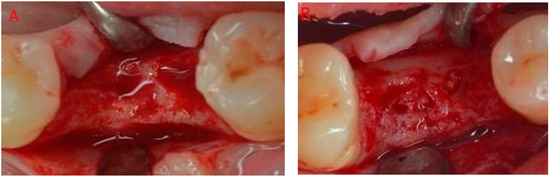

2.1. Surgical Protocol